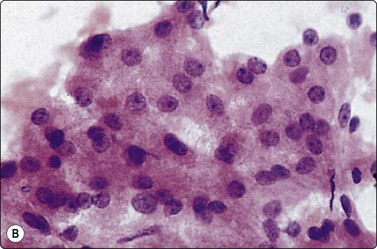

image image

Fig. 10.15 Hepatocellular carcinoma

(A) Cells are typically arranged in widened trabeculae (Pap, IP); (B) Less commonly in acinar arrangements (cell block H&E, IP).

The characteristic findings relate to (1) cell groupings, (2) relationship to endothelium and (3) cell morphology.39,41,72,79,116-132

The features in any individual FNA sample are extremely variable and largely dictated by tumor differentiation.116,117,127,132 As the degree of differentiation decreases, the cells become more obviously malignant and their resemblance to hepatocytes decreases.

Smears are typically cellular with large fragments, clusters and dispersed cells (Fig. 10.14). Cell groupings are classically trabecular (Fig. 10.15A), particularly in better-differentiated tumors. Acinar arrangements may be seen in up to 40% of HCC (Fig. 10.15B).72 With decreasing differentiation, smaller sheets and single-lying cells become more frequent. A reticulin stain on smears or cell block material may highlight the widened trabeculae and/or acinar structures or the reduced or absent reticulin (Fig. 10.16). Endothelial relationships to HCC cell groups are an integral part of the diagnosis. Endothelial cells of sinusoidal capillaries may traverse (Fig. 10.17) or enclose (Fig. 10.18) trabeculae or separate tumor cell groupings.128 This important diagnostic criterion is diminished and then lost with decreasing differentiation.

The cells resemble hepatocytes, thus demonstrating polygonal outlines and dense, granular cytoplasm, but with increased nucleocytoplasmic ratios over normal counterparts (Fig. 10.19). Centrally placed nuclei, characterized by granular to coarse chromatin, show cytoplasmic invaginations (intranuclear inclusions) in up to 70% of cases and large central nucleoli in up to 60% of cases. One of the most outstanding cytological appearances in HCC is the presence of many stripped malignant nuclei with identical characteristics, lying free in the background between cell groups (Fig. 10.20).126 The presence among malignant cells of occasional tumor giant cells or of bizarre hepatocytes would seem to favor primary liver carcinoma as they are rare in metastatic carcinoma.72,131 Bile pigment within the cytoplasm and between the cells proves the hepatocellular origin of the tumor, but is demonstrable in only 25% of cases (Fig. 10.21). Fouchet’s reagent counterstained with hematoxylin/Sirius red stains bile intensely green (Fig. 2.19). Contaminant benign hepatocytes and bile duct epithelium may be collected from the surrounding non-neoplastic liver, particularly in the setting of cirrhosis. They usually lie apart from the tumor cells.